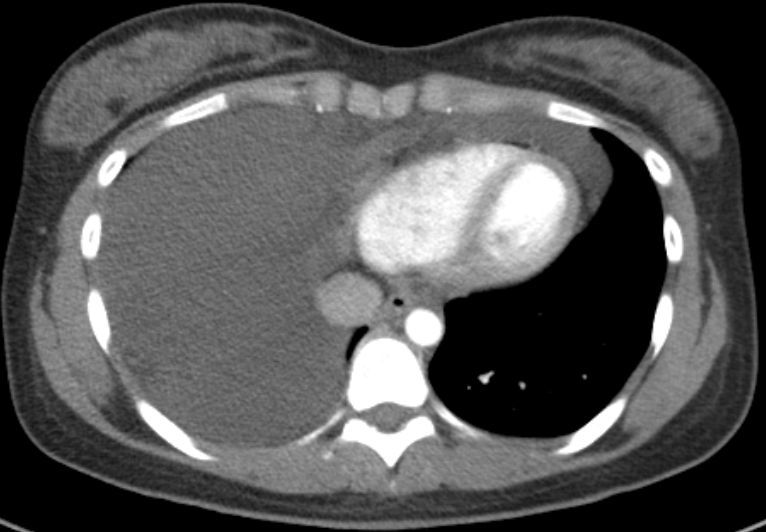

前纵隔结节前纵隔肿块胸腺囊肿thymiccyst和胸腺瘤如何区别需要手术吗